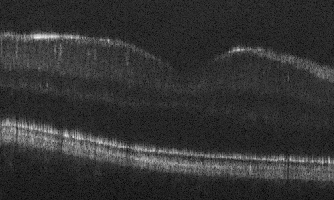

In Fig. 2 we show the denoising results of our model for a range of values. is the original input image for each SNR level. Increasing values indicate more denoising steps. The best result (determined visually) for each noise level, as highlighted by the red box, coincide with the intuition that the noisier images benefit from a larger . For the third column, where the input noise level is relatively low, we can see that as increases from 41 to 51, retinal layers gradually become over-smoothed and fine texture features fade away. As discussed in Sec. 2, Eq. 10 explains that the denoising process is done by adding Gaussian noise to compensate for the speckle pattern. When the is too large (e.g. in Fig. 2), the added noise becomes excessive and produces poor results.

We further note that our proposed method performs well for vessel and layer preservation. For example, in the second column, our result reveals the very thin external limiting membrane (ELM) (marked by red arrows) which is hardly visible in the noisy input.